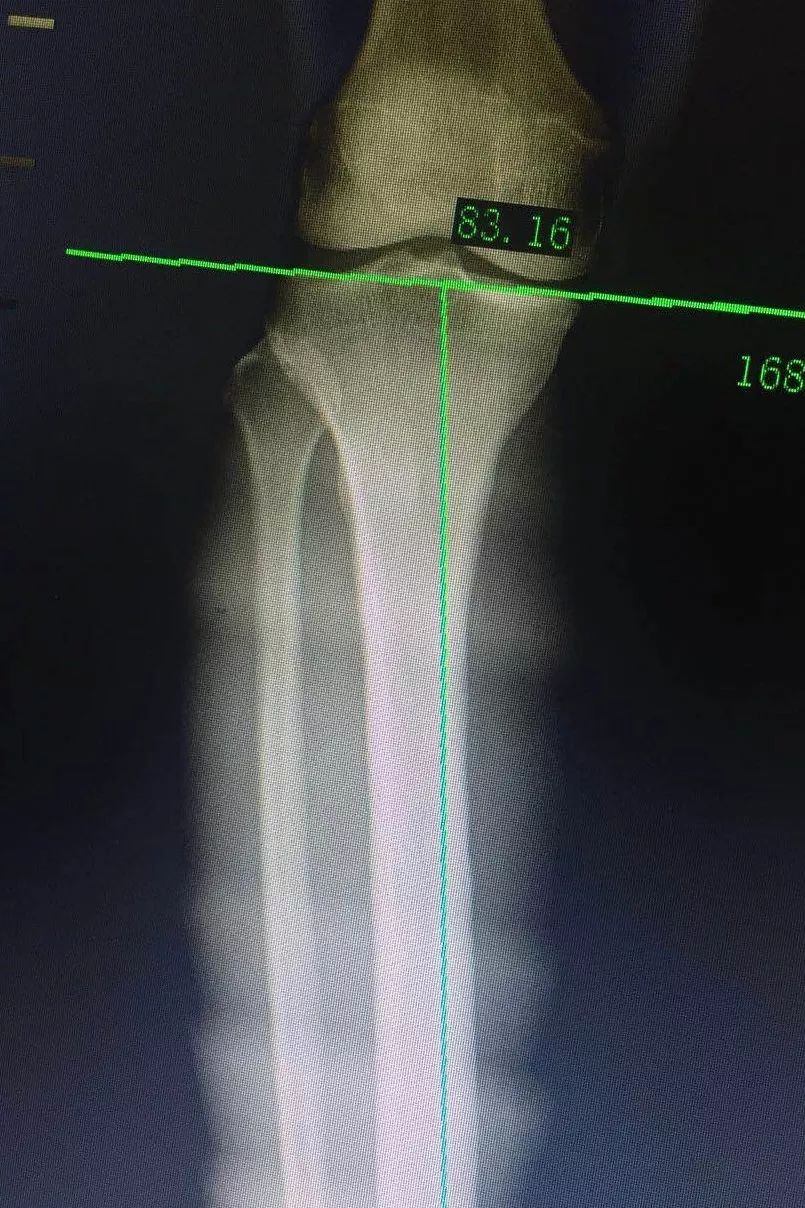

台州市中西医结合医院成功完成一例关节镜下关节清理 胫骨高位截骨术